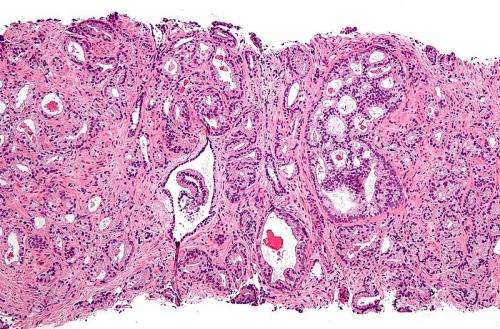

为了确定HSD17B4在前列腺癌转变为CRPC过程中发挥的作用,Sharifi博士的团队分析了该基因在健康人体、局部前列腺癌病人和CRPC病人前列腺组织中的表达情况。他们发现HSD17B4表达水平在健康和局部前列腺癌组织中相当,但是CRPC组织中显著降低,这表明HSD17B4在防止前列腺癌进展为CRPC过程中确实发挥着作用。

通过一系列分析,研究人员发现只有一种特殊的亚型-2型HSD17B4才能使雄性激素失活,防止肿瘤生长。它在早期前列腺癌组织中表达,但是在CRPC中被抑制或者缺失。

研究人员也在临床前研究中确证了他们的发现。他们的发现表明缺失2型HSD17B4会导致晚期CRPC。他们将进行进一步研究以探索HSD17B4在CRPC中如何被抑制以及它是否可以作为生物标记物预测病人始于前列腺癌的风险。